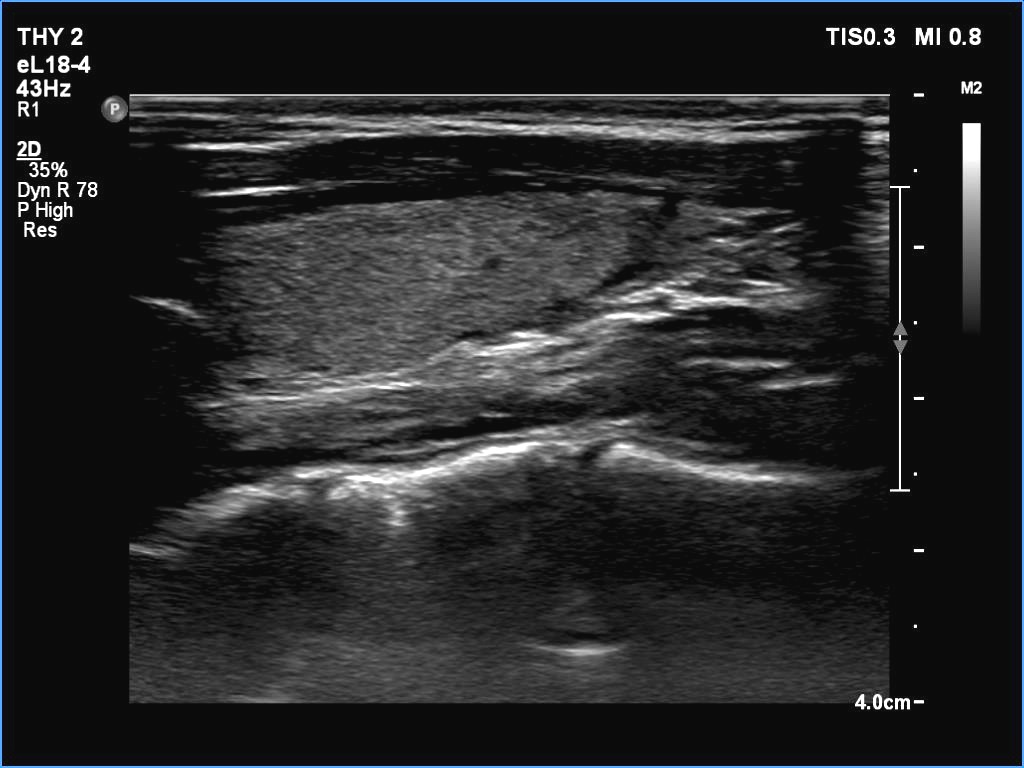

Introduction - case 745 (ultrasonographic picture 15)

Left lobe, longitudinal scan.